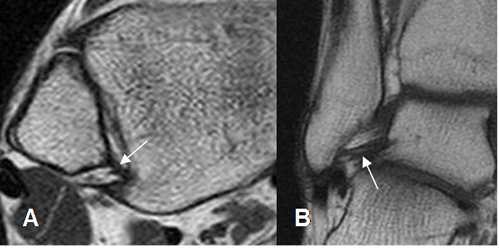

Fig 16. Ligamento tibiocalcáneo normal.

A: RM axial y B: RM coronal en T1.

Fig 17. Ligamento calcaneoescafoideo.

A: RM axial en T1 y B: RM sagital en T2. Ligamento hipointenso normal, entre el escafoides y el calcáneo.